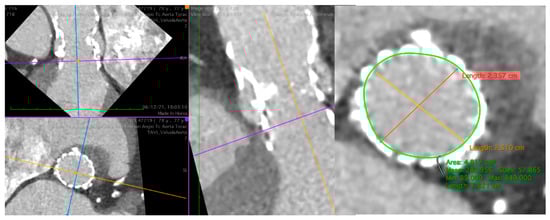

Figure 3.

Pre-procedural CT of the aorta with a degenerated Evolut R 29. At SOV, evidence of an area of 4.8 cm2 and a perimeter of 78 mm suitable for a Sapien 3 23. CT, computer tomography; SOV, Sinus of Valsalva.